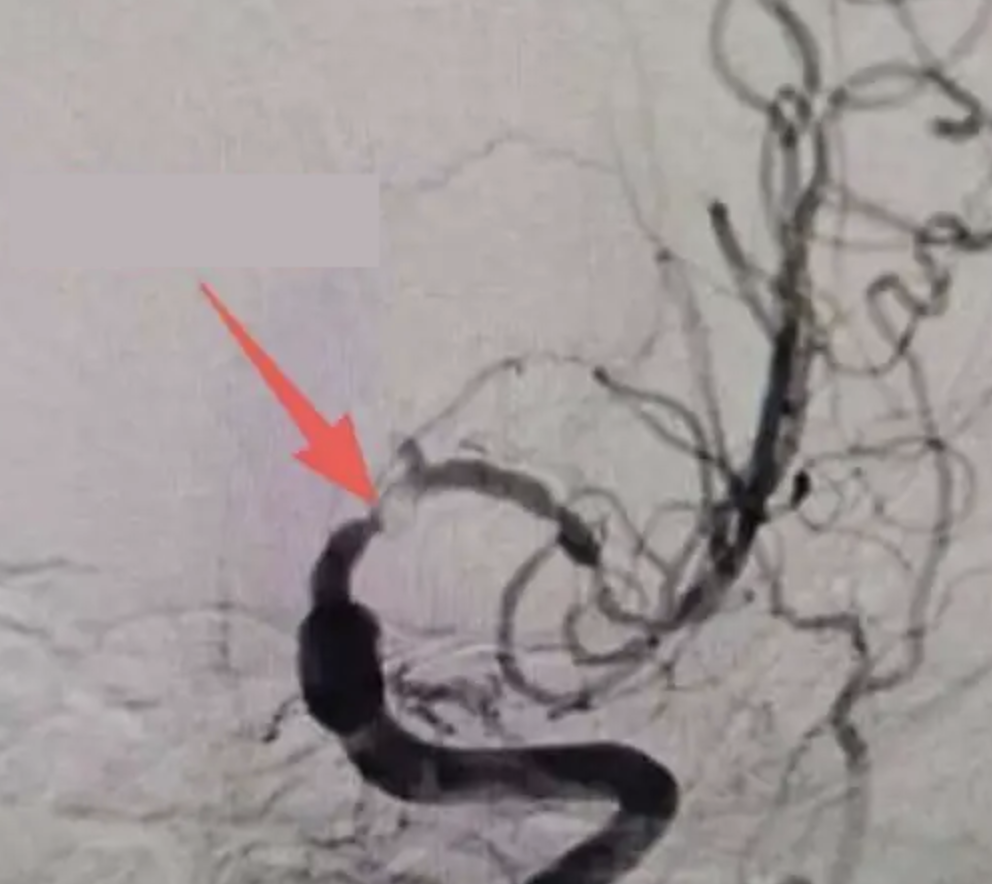

Bác sĩ Chu Nghị, làm việc tại khoa Thần kinh của bệnh viện cho biết, kết quả chụp cộng hưởng từ (MRI) cho thấy trong não ông có ổ nhồi máu mới gây đột quỵ nhồi máu não. Ảnh chụp mạch máu não phát hiện động mạch não trái bị hẹp nghiêm trọng, nếu không điều trị kịp thời có thể dẫn tới liệt nửa người hoặc thậm chí gây tử vong do đột quỵ.

Bác sĩ Tiêu Khả Cẩm, trưởng khoa Thần kinh của bệnh viện đã ngay lập tức chỉ định chọc dò tủy sống và phân tích dịch não tủy. Kết quả khám cho thấy ông Ôn mắc bệnh giang mai thần kinh mạch máu não . Bệnh khởi phát do xoắn khuẩn Treponema pallidum xâm nhập hệ thần kinh trung ương, gây viêm thành động mạch não, tạo thành cục huyết khối gây tắc hẹp mạch máu não, từ đó tăng nguy cơ đột quỵ và nhiều hệ lụy nghiêm trọng khác. Bệnh giang mai thần kinh mạch máu não có thể phát triển trong vài tháng đầu đến vài năm sau khi nhiễm giang mai.

Sau khi xác định nguyên nhân gây bệnh, các bác sĩ đã hội chẩn và lên phác đồ điều trị cho ông Ôn. Bệnh nhân được dùng penicillin tiêm tĩnh mạch liều cao nhằm tiêu diệt vi khuẩn và kiểm soát tình trạng viêm mạch. Đồng thời, bệnh nhân cũng phải sử dụng thuốc phòng ngừa đột quỵ tái phát.

Bệnh nhân đáp ứng thuốc điều trị giang mai nên tình trạng viêm và hẹp mạch máu não đã cải thiện đáng kể. Bệnh nhân không cần phải phẫu thuật đặt stent mạch máu não để tái thông dòng máu. Hiện, ông Ôn đang tiếp tục điều trị và theo dõi tại bệnh viện.